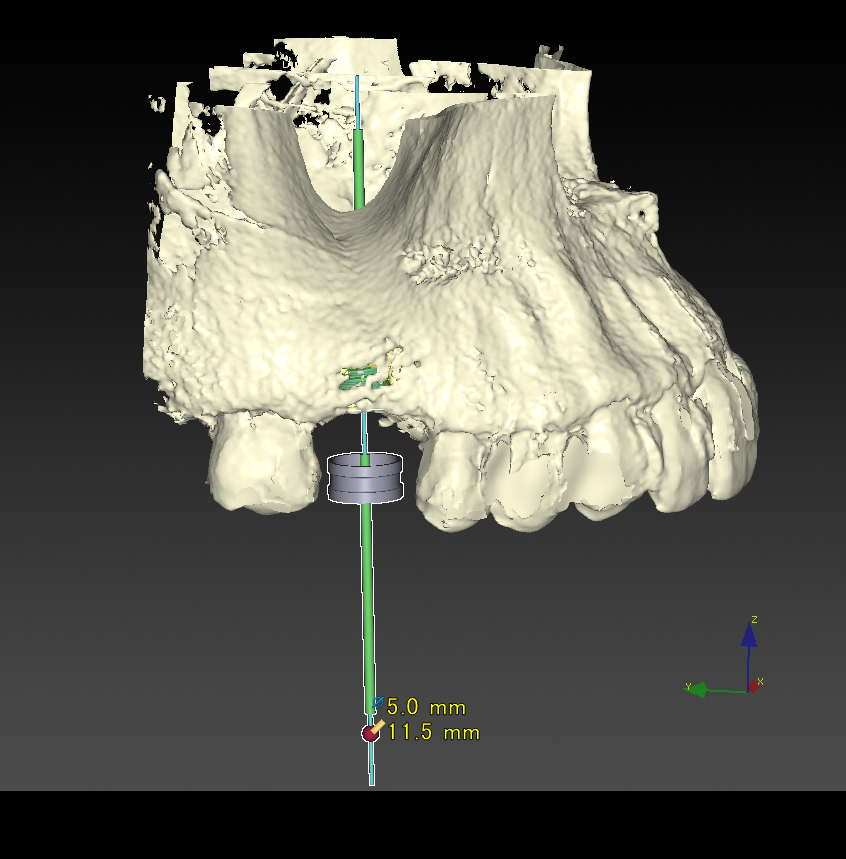

CT撮影で立体的な顎の骨を確認できます。

CTシミュレーション

CTデータをインプラント解析ソフトに入れ、手術のシミュレーションをします。

・骨の状態を確認し、骨造成が必要か見極めます。

・シミュレーションでインプラントが可能か確認し、インプラントのサイズを調べます。

治療計画の説明

コンサルティングでシミュレーション結果を解説します。

見積もりをお渡しします。